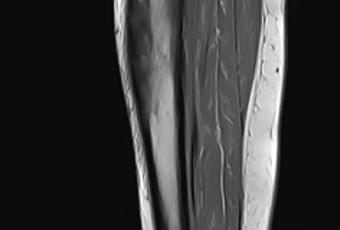

Se realizaron cortes sagitales, axiales y coronales con técnica de espín eco con el protocolo habitual.

Se identifican edema en el tejido celular subcutáneo adyacente a la tibia y grupos musculares en la región anterior y medial de la pierna.

Existen cambios en la morfología e intensidad del hueso esponjoso de la tibia que involucra la diáfisis proximal y tercio medio con áreas de baja intensidad en el hueso esponjoso medular así como de mayor intensidad, la cortical al parecer se encuentra conservada.

La intensidad de las estructuras musculares se encuentra conservada.

Edema en el tejido celular subcutáneo adyacente a la tibia y grupos musculares en la región anterior y medial de la pierna.

Existen cambios en la morfología e intensidad del hueso esponjoso de la tibia que involucra la diáfisis proximal y tercio medio con áreas de baja intensidad en el hueso esponjoso medular así como de mayor intensidad, la cortical al parecer se encuentra conservada, cambios de proceso infiltrativo óseo de etiología a determinar.